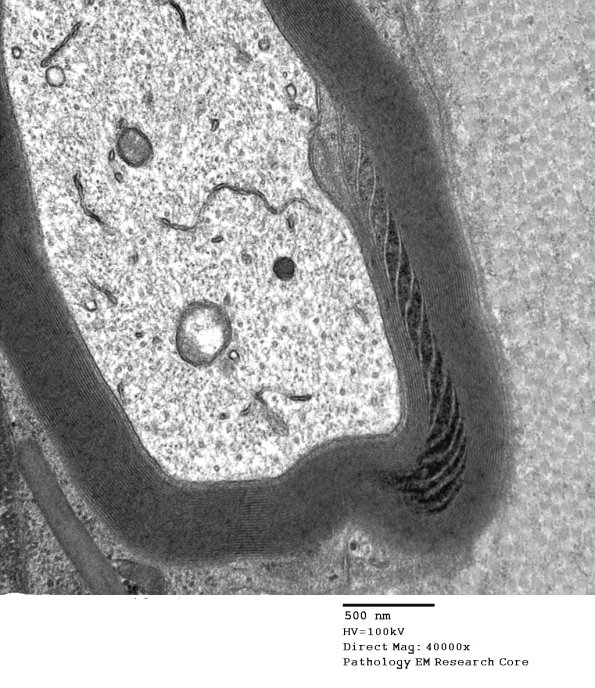

Higher magnification of image #7A1. (electron micrograph)